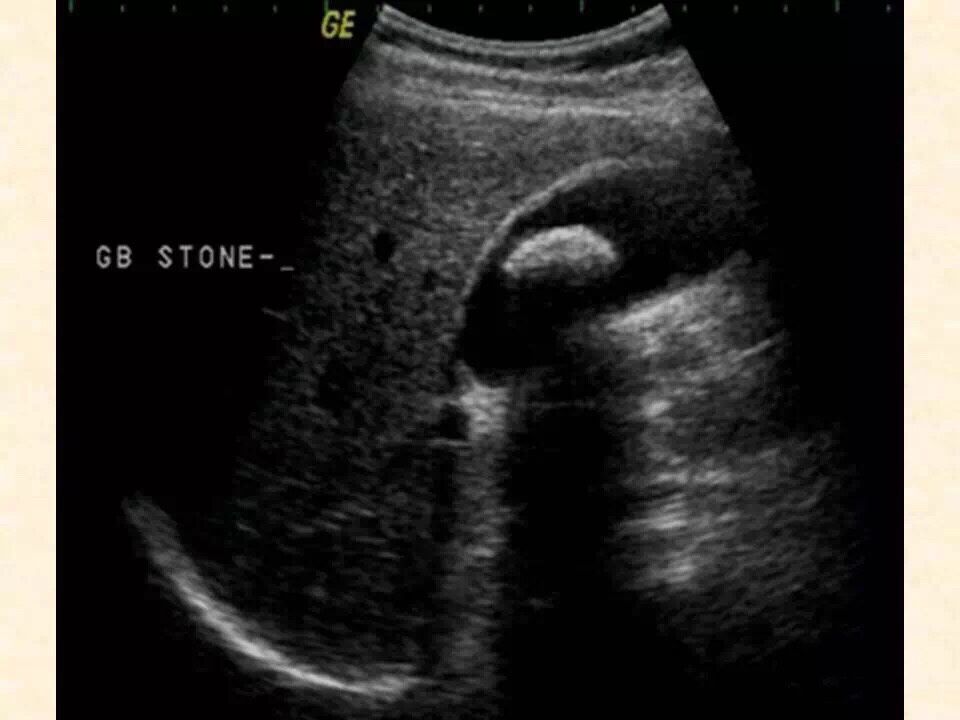

1、消化系统:肝胆胰脾的超声检查。

6、超声引导下的介入诊断及治疗(肝肾囊肿及脓肿穿刺,抽吸,药物灌注,胸腔,纵膈的穿刺活检)